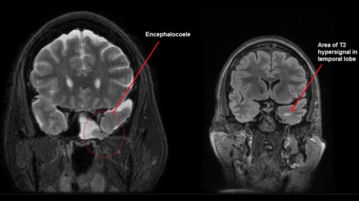

Training Brain Cells to Stop Epilepsy

SAN DIEGO, Calif. (Ivanhoe Newswire) – More than three million Americans suffer from epilepsy. Not knowing when or if a…More